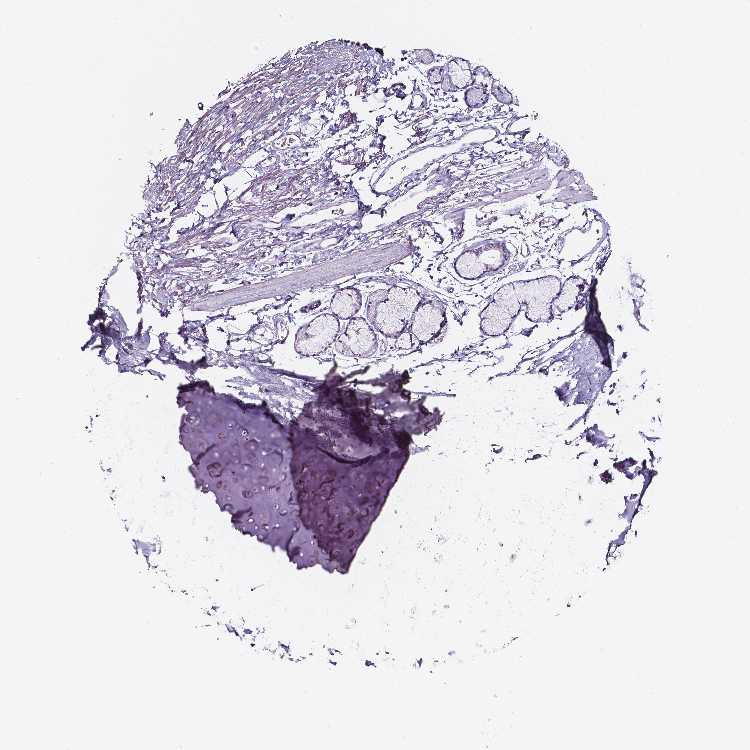

SOFT TISSUE 2 - Antibody stainingi

Antibody staining in the annotated cell types in the current human tissue is reported as not detected, low, medium, or high, based on conventional immunohistochemistry profiling in selected tissues. This score is based on the combination of the staining intensity and fraction of stained cells.

Each image is clickable and will lead to virtual microscopy that enables deeper exploration of all samples and also displays staining intensity scores, fraction scores and subcellular localization as well as patient and tissue information for each sample.

Antibody HPA020280Antibody CAB070163

Fibroblasts Not detectedNot detected

Peripheral nerve Not detectedNot detected